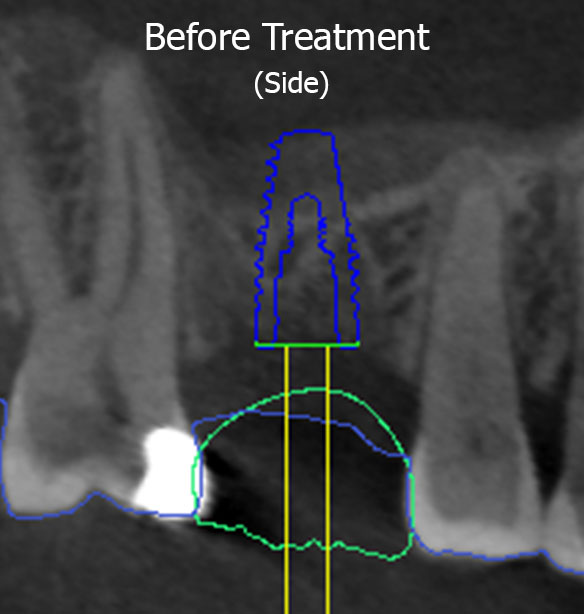

DM had a missing tooth on the top right side and wanted an implant in that area so that he could chew properly again. Planning with digital dentistry found that his sinus had grown in size as a result of the removal of the tooth (as shown by the red dotted line), meaning there was not enough height of jaw bone to support an implant in this area without causing a puncture into the sinus (shown by the transparent overlay of the planned implant site going beyond the red dotted line). As mentioned above, a puncture into the sinus can cause a serious infection with dire consequences.

A sinus lift procedure was performed for DM, which lifted the floor of the sinus and resulted in more bone forming (shown by the green dotted line and the transparent overlay of the implant no longer going beyond the green dotted line). This allowed enough bone height in the jaw to facilitate placement of the implant and subsequent crown on top. DM is now able to chew and eat food on high right side, without having a serious sinus infection as a byproduct!